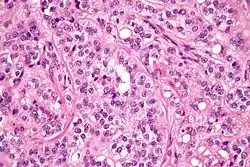

Micrograph of a Leydig cell tumour -

Micrograph of a Leydig cell tumour